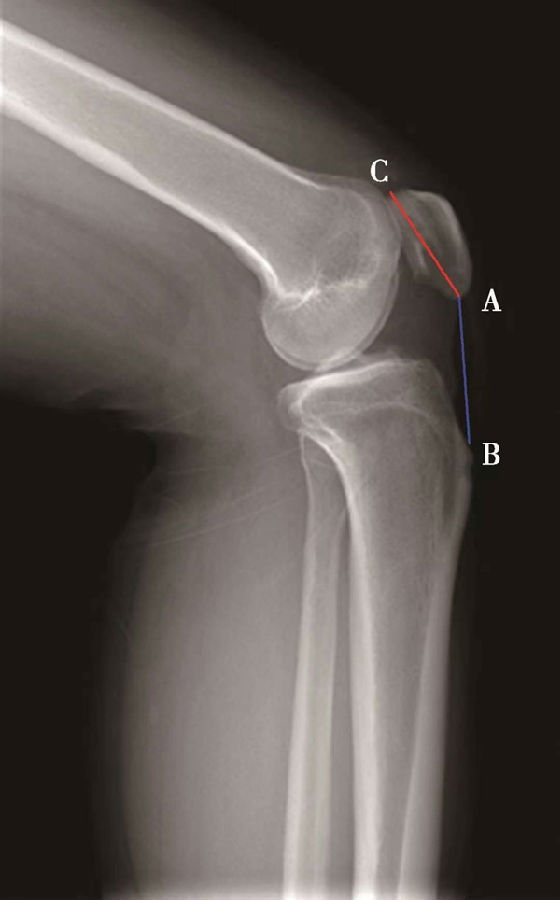

如图示:AB是髌骨关节面最低点到胫骨平台延长线的垂直距离。AC是髌骨关节面的长度。BlackBurne-Peel指数=AB/AC(图7)。

图7 BlackBurne-Peel指数=AB/AC=0.80,为正常髌骨高度

图8 BlackBurne-Peel指数=AB/AC=1.20,为高位髌骨